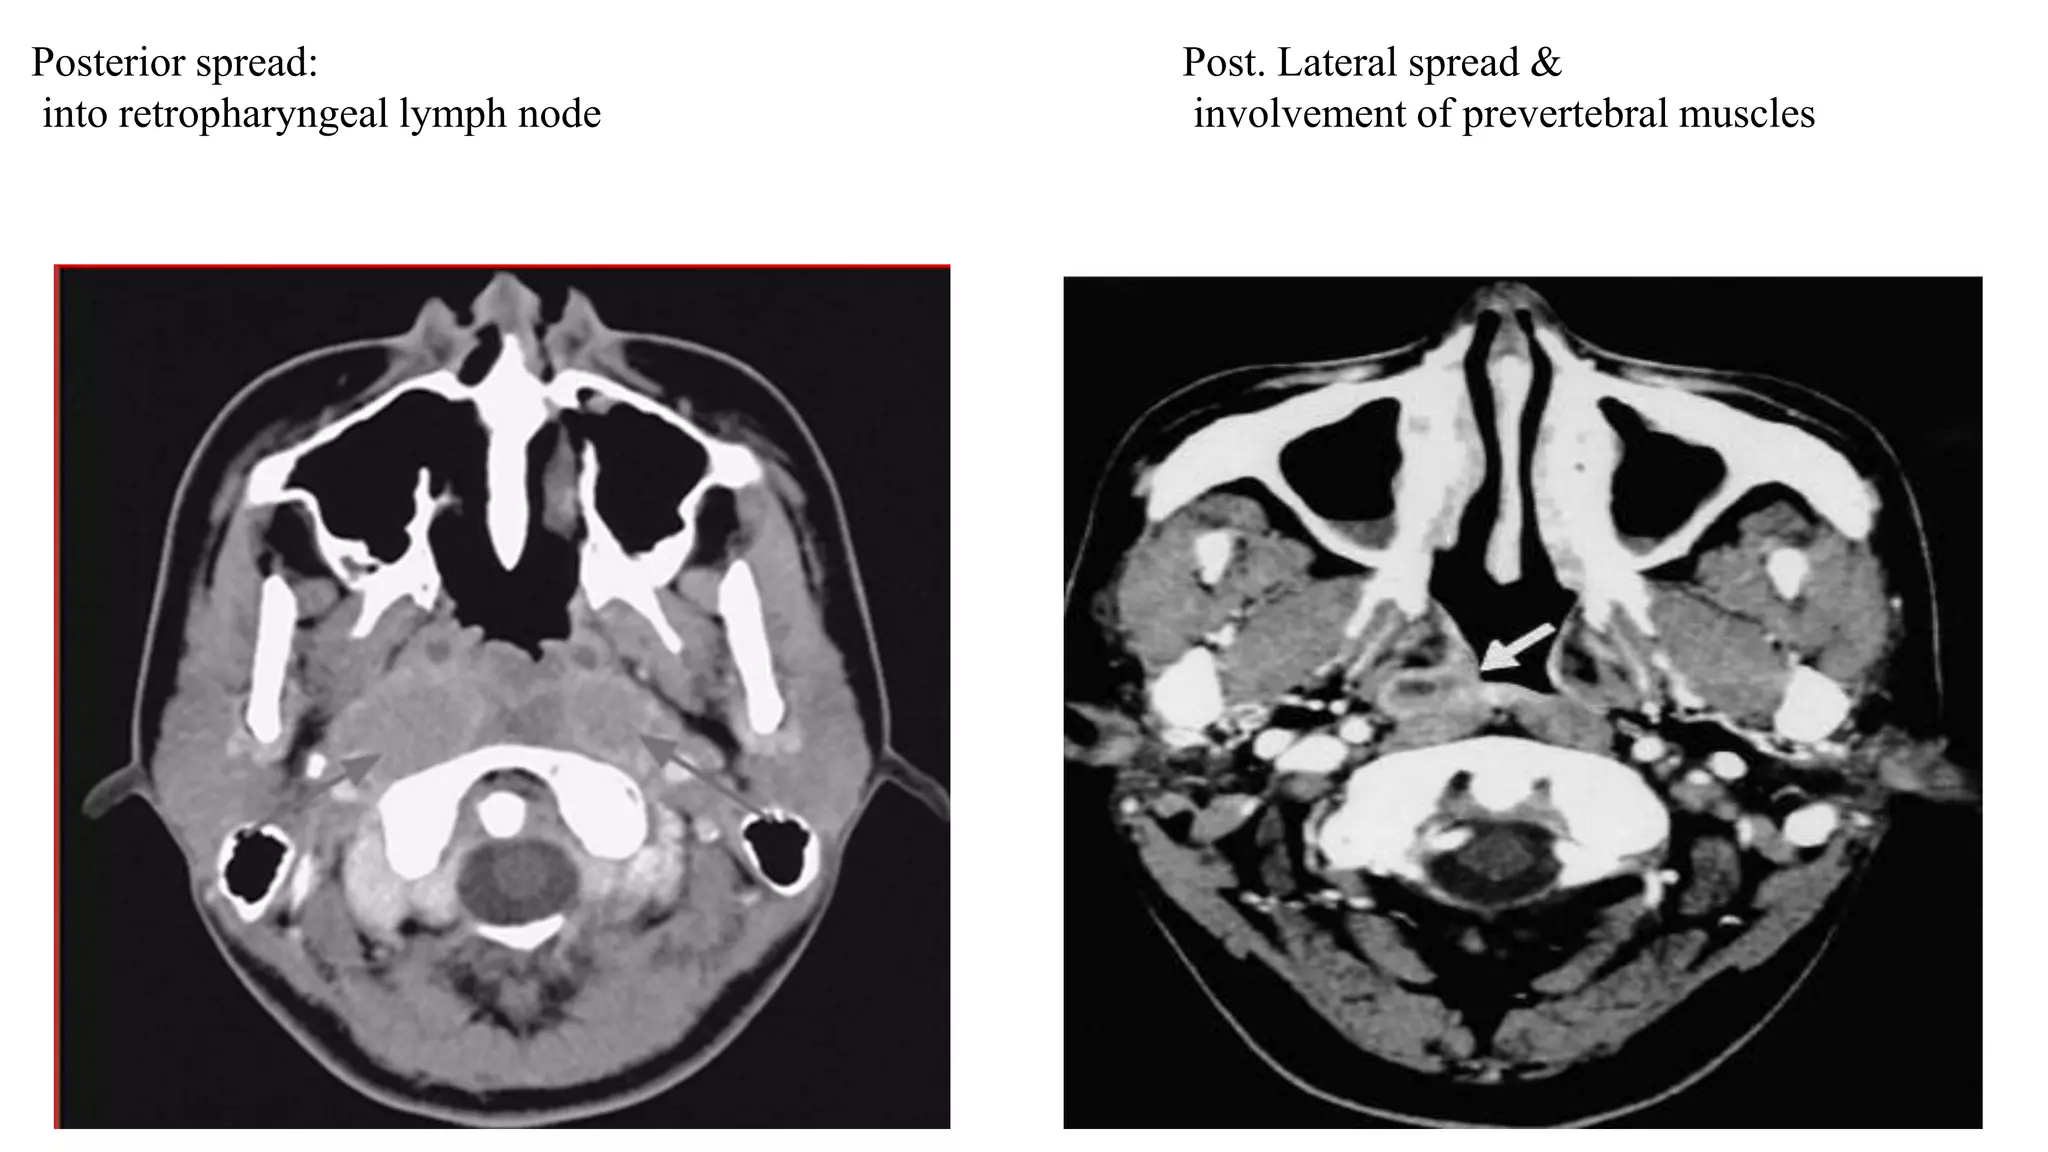

Posterior spread:

into retropharyngeal lymph node

Post. Lateral spread &

involvement of prevertebral muscles